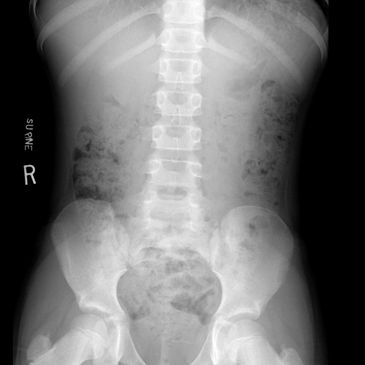

- Constipation in children